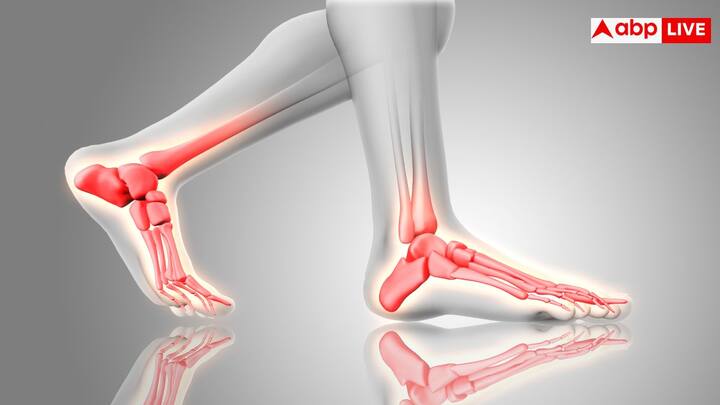

डॉक्टर इस सामग्री को टूटी हड्डी पर लगाएंगे. यह हड्डी की कोशिकाओं को सहारा देकर नई हड्डी बनने में मदद करेगी.

इसकी बनावट स्पंज जैसी है जिसमें छोटे-छोटे छेद होते हैं. इससे पोषक तत्व आसानी से फैलते हैं और हड्डी जल्दी जुड़ती है.

यह तकनीक फ्रैक्चर, दांतों के इम्प्लांट और ऑस्टियोपोरोसिस के मरीजों के लिए बहुत फायदेमंद है. इलाज का समय कम होगा.

वैज्ञानिकों ने इसे चूहों पर टेस्ट किया. नतीजे दिखाते हैं कि यह हड्डी बनाने की प्रक्रिया को तेज कर देती है.

यह सामग्री शरीर में घुल जाती है और नई हड्डी जैसी ही मजबूत हड्डी बनाती है. इसकी ताकत और बनावट प्राकृतिक हड्डी जैसी है.